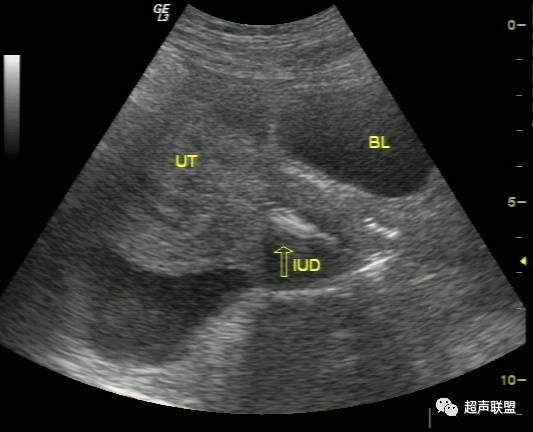

在耻骨联合上方做纵切、横切、斜切观察子宫形态、大小、子宫内膜厚度、宫腔内有无妊娠囊,双侧附件区及盆腔有无明显包块及液性暗区。并观察肝肾间隙、脾肾间隙及腹腔两侧有无液性暗区。

超声检查声像图特点:

(1)子宫增大或轻度增大,子宫内膜不同程度增厚,宫内未见妊娠囊。

(2)一侧附件区可探及不均质包块,包块形态欠规则,边界不清楚,回声紊乱。

(3)陶氏窝:可见多少不一不规则的液性暗区,暗区中有密集点状回声。

宫外孕破裂出血的声像图 宫外孕发生率占妊娠的0.5%~1%,其中95%为输卵管妊娠。常与输卵管炎、输卵管手术后输卵管不同程度粘连、受精卵移行不畅有关。输卵管妊娠时由于缺乏完整蜕膜,孕卵植入后,其绒毛借蛋白分解酶的作用直接侵蚀管壁肌层,因输卵管管壁薄弱,不能适应受精卵的发育,当受精卵发育到一定程度后,常引起流产或破裂。由于输卵管肌层血管丰富,短期内即可大量出血使患者陷入休克。由于破裂口周围形成凝血块或未凝血液,从而超声表现为形态不规整、边界不清楚、回声紊乱的混合性包块,并有盆腔积液,积液中含血细胞形成的密集点状回声。

宫外孕破裂出血是妇产科最常见的急腹症之一。出血量大者,病情特别危急,需要立即作出诊断和鉴别诊断,以便采取适当而有效的治疗措施。对于一个临床主要表现为下腹剧痛,超声表现为:子宫轻度增大,子宫内膜不同程度增厚,宫内未见妊娠囊;一侧附件区可探及不均质包块,包块形态欠规则,边界不清楚,回声紊乱;陶氏窝可见多少不一不规则的液性暗区,暗区中有密集点状回声。盆腔甚至腹腔积液的妇产科急症患者。检查者应该想到上述疾病。并尽可能详细询问月经史、性生活史及临床病史,结合尿或血HCG检查、血常规检查等,进行综合分析判断。随着超声仪技术的发展,阴道彩色多普勒检查的应用,宫外孕包块内滋养层血流的检测,将更有助于宫外孕破裂的诊断及鉴别诊断。